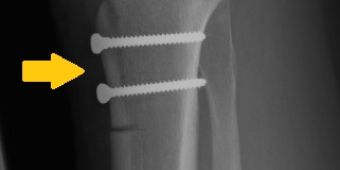

patellazentrierung

Tuberositasversatz und Knochenfixierung (Pfeil) mit zwei Zugschrauben. © Asklepios

• knöcherne Eingriffe: in einigen Fällen besteht bereits eine anlagebedingte Fehlform / -position der Kniescheibe oder ein zu flaches Gleitlager im Oberschenkelknochen, so dass die Kniescheibe keine ausreichende Führung hat. In diesen Fällen ist eine Vertiefung des Gleitlagers (sog. Trochleaplastik) oder eine Zentrierung der Kniescheibe in das Gleitlager durch einen Knochenversatz (Bild) (sog. Tuberositasversatz) möglich.